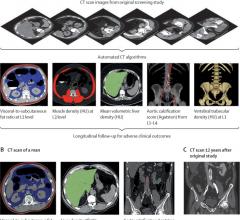

June 6, 2024 — In a landmark study, the latest in technology innovation by Konica Minolta Healthcare was used to develop ...